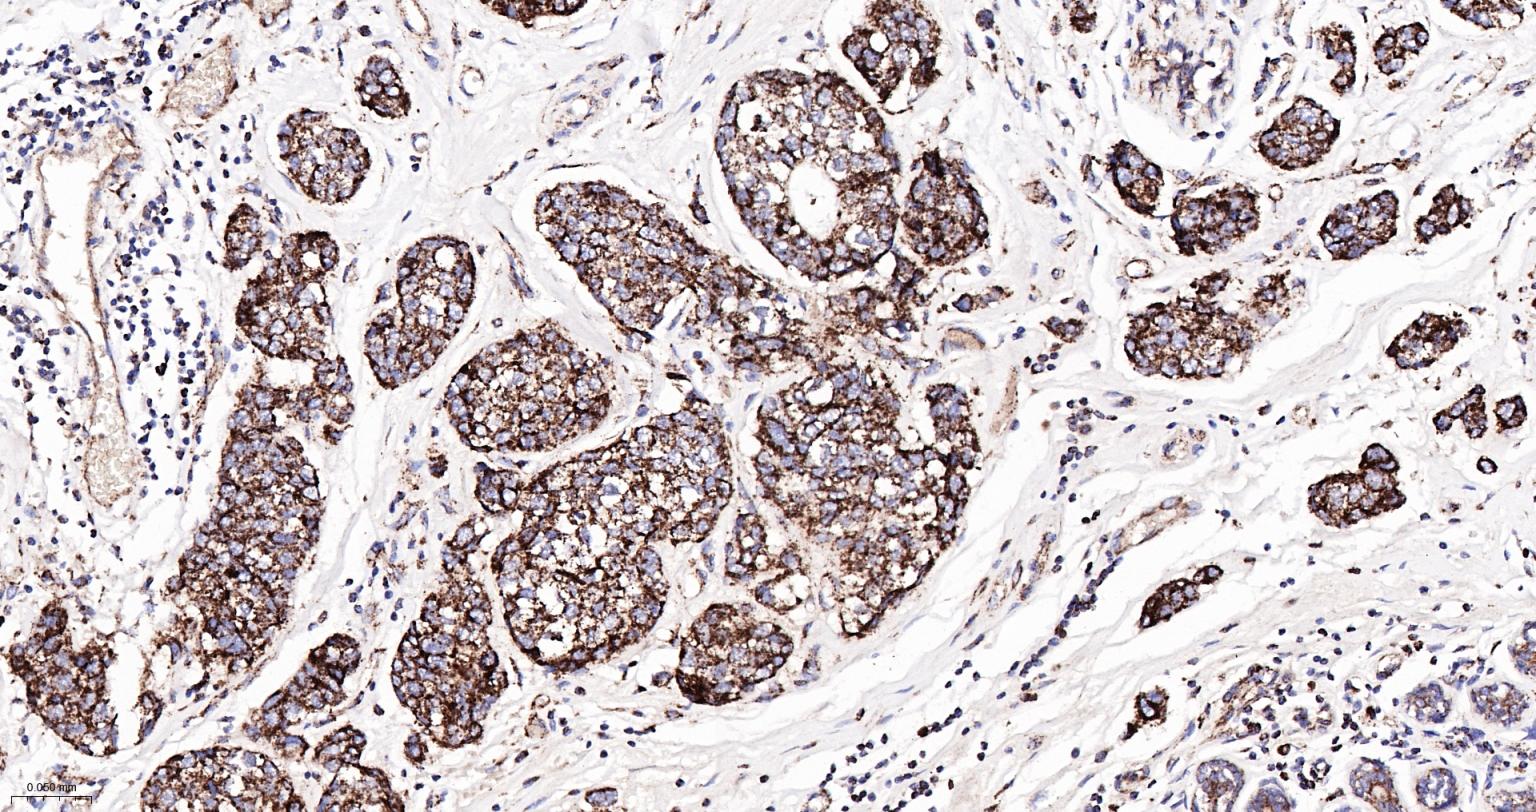

Paraformaldehyde-fixed, paraffin embedded Human Breast Cancer; Antigen retrieval by boiling in sodium citrate buffer (pH6.0) for 15 min; The section was incubated with Cytochrome C Monoclonal Antibody, Unconjugated (bsm-52050R) at 1:200 overnight at 4°C, followed by conjugation to the bs-0295G-HRP and DAB (C-0010) staining.